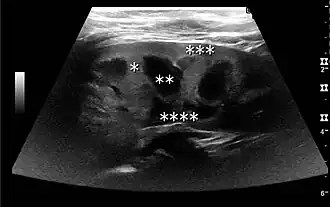

Complex cysts can have membranes dividing the fluid-filled center with internal echoes, calcifications or irregular thickened walls. The complex cyst can be further evaluated with Doppler US, and for Bosniak classification and follow-up of complex cysts, either contrast-enhanced ultrasound (CEUS) or contrast CT is used (Figure 6). The Bosniak classification is divided into four groups going from I, corresponding to a simple cyst, to IV, corresponding to a cyst with solid parts and an 85–100% risk of malignancy.[1] In polycystic kidney disease, multiple cysts of varying size in close contact with each other are seen filling virtually the entire renal region. In advanced stages of this disease, the kidneys are enlarged with a lack of corticomedullary differentiation (Figure 7).[1]

Figure 7. Advanced polycystic kidney disease with multiple cysts.[1]